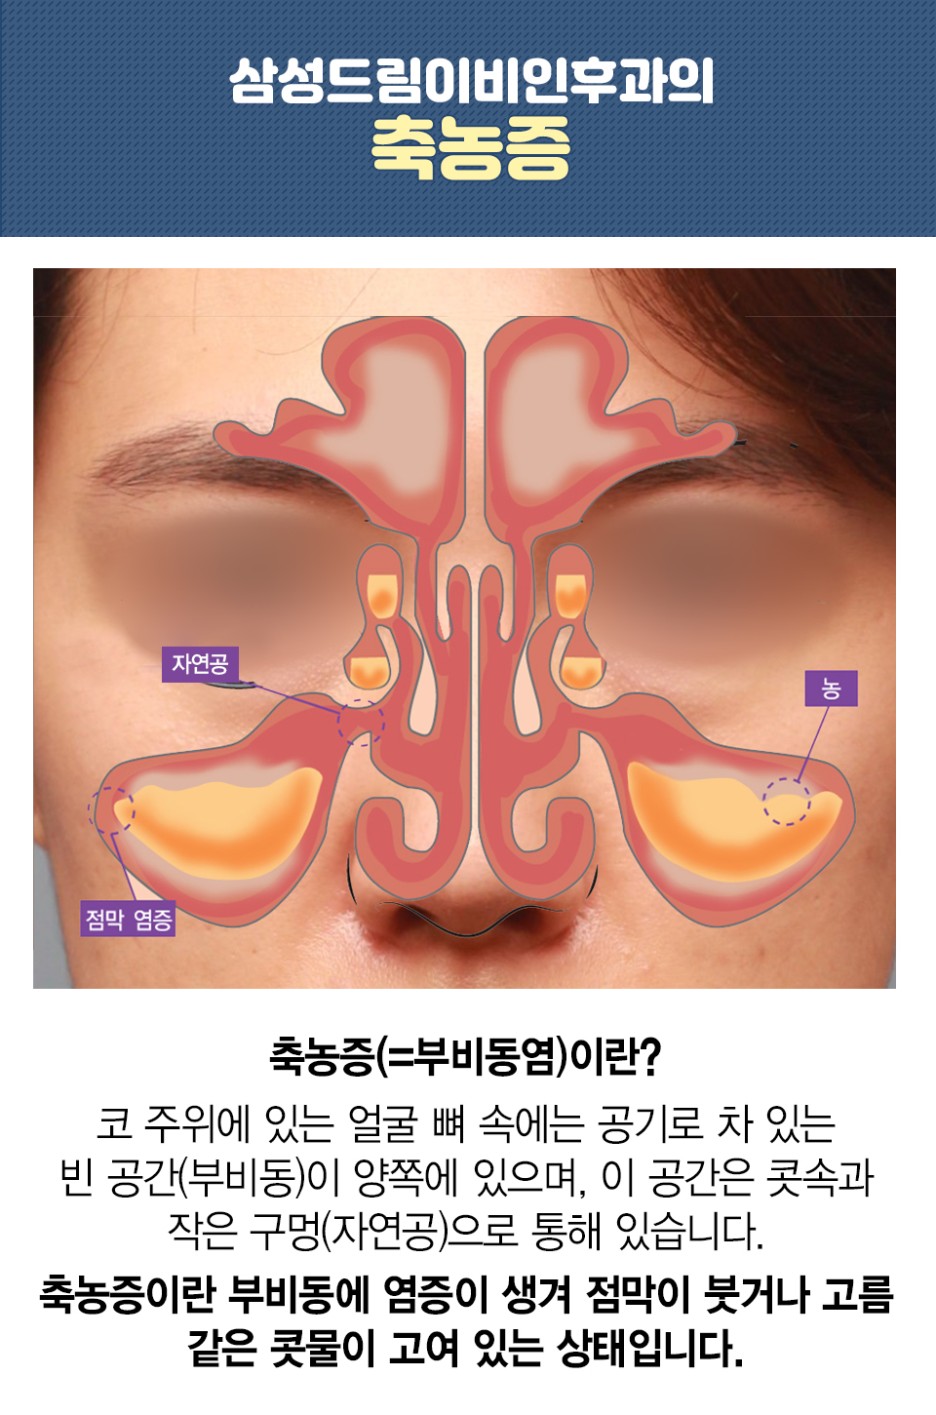

고민하는 질환이 축농증이라고 할 수 있습니다. 축농증은 의학적으로 부비강염이라고 할 수도 있습니다. 얼굴 내부에 비어 있는 공간을 가리키고 있었습니다. 이곳은 숨을 쉴 때 공급되는 산소에서 환기를 시키고 온도 조절을 통해 노폐물을 배출할 수 있도록 하는 역할이었습니다.

해당 부위에 염증이 발생하거나 문제가 나타날 경우 원활하지 않은 환기기능 문제로 염증이 심해질 수 있으며 이로 인한 코막힘 증상도 확인할 수 있었습니다. 이런 상황에서 오랜 시간 불편함이 지속되고 코의 기능적인 능력 감퇴를 시킬 수 있기 때문에 관심을 갖고 돌보는 것이 중요했습니다.

코막힘의 경우 이런 증상으로 보입니다. 일시적으로 발생하는 것이 아니라 지속되는 증상으로 이어진다면 어떤 원인이 있다고 의심할 필요가 있었습니다. 이런 상황을 방치하면 호흡은 물론 편두통이나 코 내부 이물감까지 다양한 발생을 할 수 있기 때문에 무시하고 방치하면 큰 영향을 줄 수 있었습니다.